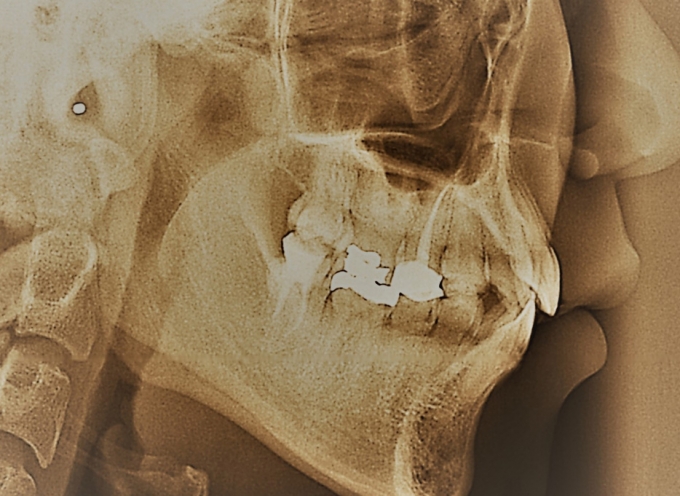

On average, a dental restoration lasts five to 10 or so years before needing replacement. The time frame depends on the type of restoration and how well the patient cares for the treated tooth. However, the continual onslaught of chewing, acidic and hard foods, poor hygiene, nighttime tooth grinding, generally weak teeth and even inadequate dental work can contribute to a filling’s early demise — and another expensive and possibly less-than-pleasant experience in the dental chair.

According to Ahn, one of the primary reasons restorations fall out or crack is brittle failure of the bond with the surrounding tooth. “All dental composites have micro-particles to increase their rigidity and prevent their shrinkage during their curing process,” he explained. “But there’s a trade-off: When the composite gets harder, it gets more brittle.”

With enough pressure or wear and tear, a crack forms, which then propagates throughout the entire restoration. Or, the gap between the tooth and the restoration results in restoration failures, including marginal tooth decay.

This proof-of-concept, which also demonstrates no cytotoxicity, could mean tougher, more durable dental fillings. And that, in the long run, could mean fewer dental visits. Because each replacement filling also requires the dentist to file the surrounding tooth to prime its surface, given enough replacements a tooth might need to be crowned or extracted; and if not replaced, the tooth loss could have adverse consequences for the individual’s diet and health.